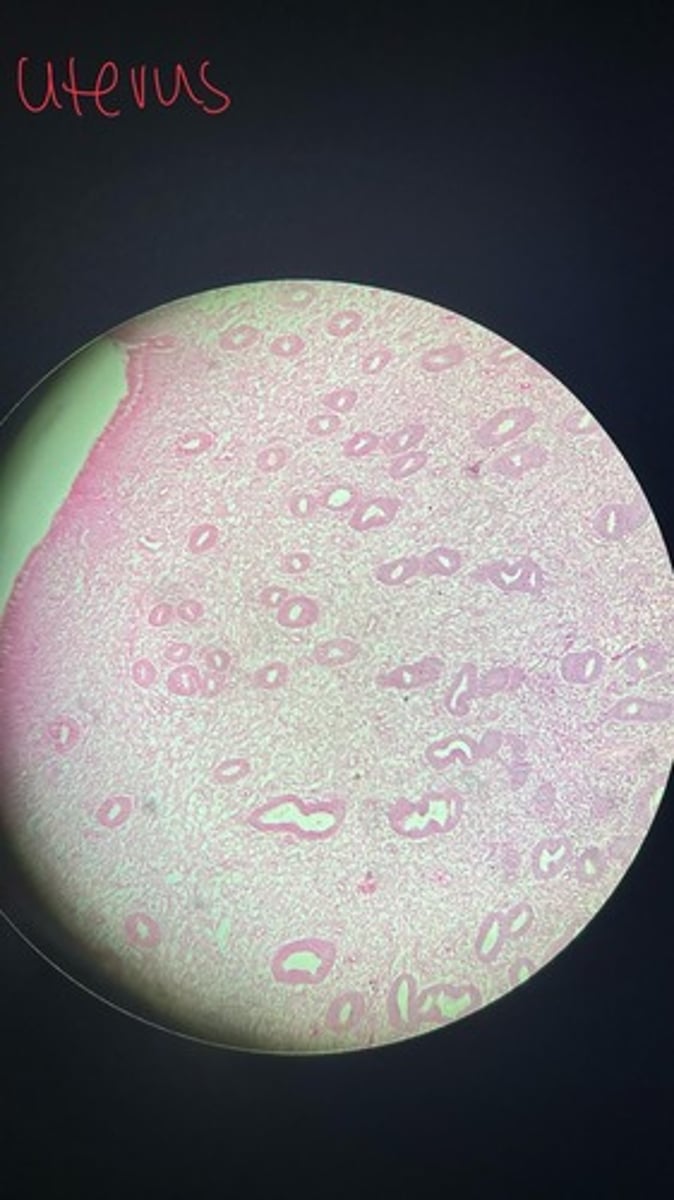

Uterus HE

Uterus HE

Uterus HE

Uterus HE